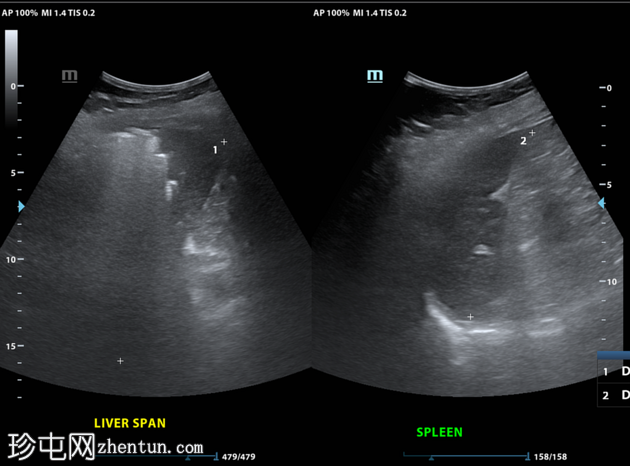

CT

轴位

非增强

肝段 6 和 7 可见多房性积液,呈环状强化

积液内可见多个气体腔

破入肝包膜下间隙,可见肝包膜下积液及气体腔

壁层腹膜与前腹壁之间可见另一局灶性积液

肝段 7 的肝内胆管局灶性扩张(0.3cm),内含气体腔

其他肝内胆管和肝外胆管均正常

胆囊缺失,可能由于既往胆囊切除术所致

无游离液体。

双侧肾皮质囊肿

轻度右侧胸腔积液伴邻近肺不张